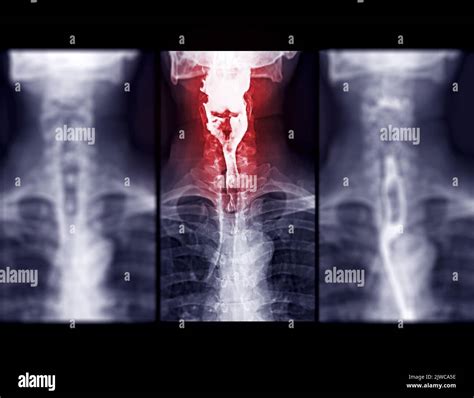

A Video Swallow Study, also known as a modified barium swallow study, is a diagnostic procedure that uses fluoroscopy to observe the swallowing process in real-time. During the study, the patient ingests barium-coated food or liquid, which makes the swallowing structures visible on X-ray images. This allows healthcare professionals to identify any abnormalities or obstructions in the swallowing pathway.

1. Patient Positioning: The patient is positioned in front of a fluoroscopy machine, which captures real-time X-ray images.

2. Barium Administration: The patient is given barium-coated food or liquid to swallow. The barium makes the swallowing structures visible on the X-ray.

3. Swallowing Observation: The healthcare provider observes the swallowing process on a monitor, noting any abnormalities or obstructions.

Interpreting the results of a Video Swallow Study involves analyzing the fluoroscopy images to identify any abnormalities in the swallowing process. Key areas of focus include:

• Oral Phase: The movement of the tongue and the coordination of the oral muscles.

• Pharyngeal Phase: The movement of the bolus (food or liquid) through the pharynx and the coordination of the pharyngeal muscles.

• Aspiration: Food or liquid entering the airway, which can lead to coughing or choking.

• Penetration: Food or liquid entering the laryngeal vestibule but not the trachea.

• Residual: Food or liquid remaining in the pharynx after swallowing.

• Delayed Pharyngeal Swallow: A delay in the initiation of the pharyngeal swallow reflex.